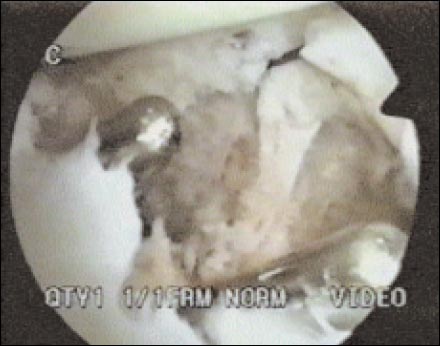

En la Sutura Transglenoidea realizamos doble túnel óseo en la unión osteocartilaginosa (Fig. 3) y tomamos 2 grupos de 3 puntos cada uno, con PDS Nº.1, tomando cápsula y rodete, (Fig. 4) los cuales pasamos con aguja y anudamos en la fascia del infraespinoso.

Figura 3: doble tunel oseo